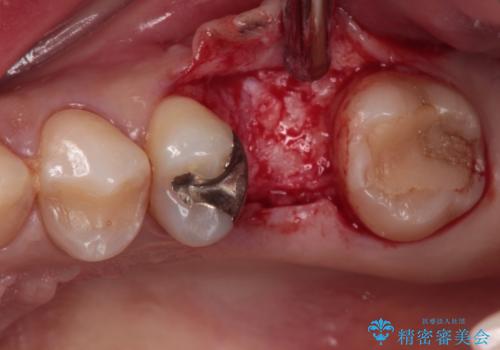

土台の材料を外して顕微鏡下で確認したところ、歯根にまで及ぶ破折が認められたため、インプラント治療を行うこととしました。

他にも銀歯や欠損となっている歯に対しての治療も希望されたため、補綴治療を行うこととしました。